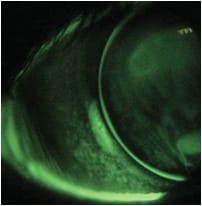

Biomicroscopy showed that the lenses positioned inferiorly with poor movement; the fluorescein patterns showed apical alignment, midperipheral touch, and minimal peripheral clearance. Biomicroscopy with the lenses removed revealed grade 2 bulbar injection interpalpebrally and moderate punctate epithelial staining at the 4 o’clock and 8 o’clock areas of the peripheral cornea OD, and grade 2 bulbar injection interpalpebrally, mild central corneal staining, an opacified area at the 8 o’clock area of the peripheral cornea with patchy staining overlying, and moderate punctate staining at 4 o’clock OS (Figure 3a).

Figure 3a. Patchy area of peripheral corneal desiccation due to low-riding GP lens.

Discussion Based on the patient’s symptoms and clinical signs, I diagnosed peripheral corneal desiccation (PCD) OD and OS, with vascularized limbal keratitis (VLK) OS. This condition results in areas of corneal surface dryness caused by tear film instability due to the presence of the contact lens. The thickness of the lens edge prevents the upper lid from rewetting the corneal surface adequately on the blink, and over time the area becomes dry. Low-riding lenses tend to exacerbate the condition because they move less, resulting in tear stagnation and blink inhibition. Other contributing factors include incomplete or insufficient blinking, poor tear film quality or quantity, and poor lens material and design selection. The patient’s work habits also contributed; extended computer work tends to reduce blink rate, making the eyes progressively drier as the day goes on.